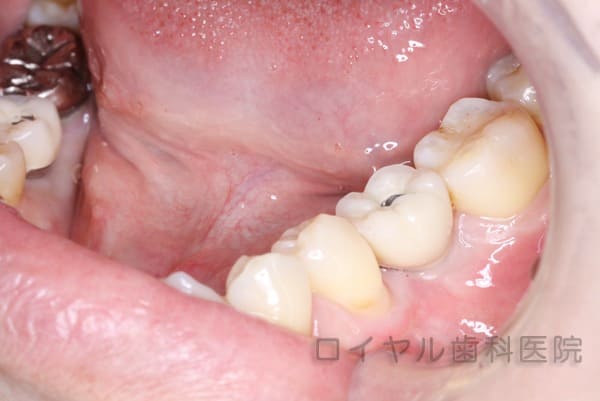

CASE2

下顎右6番、左6番のインプラント治療

術中

インプラントを埋入3ヵ月経過しています。

歯肉も健康で調和が取れています。

- 主訴

- 重度のむし歯で歯が残せない

- 治療内容

- 下顎右6番、左6番のインプラント治療

下顎右6番、左6番にインプラントを埋入したケースです。

【リスク・副作用】

お手入れが悪いと歯肉が腫れる場合があります。